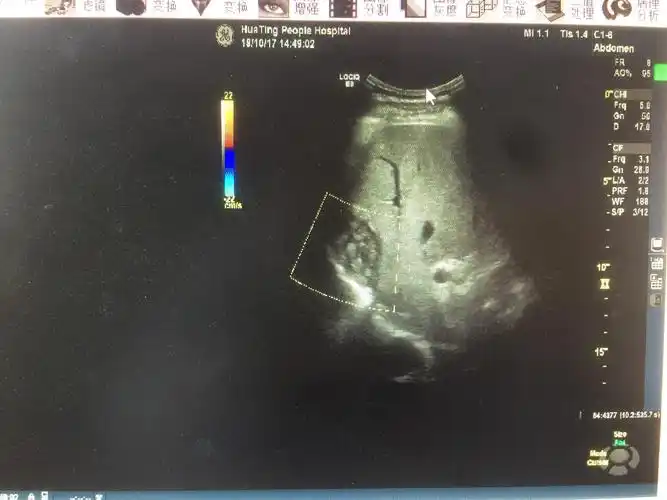

肝包虫病一例 - 超声医学讨论版 - 爱爱医医学论坛

肝包虫病?肝囊性变?

发现肝包虫,县疾控中心上报并确诊为我县域首例上报肝包虫病例.